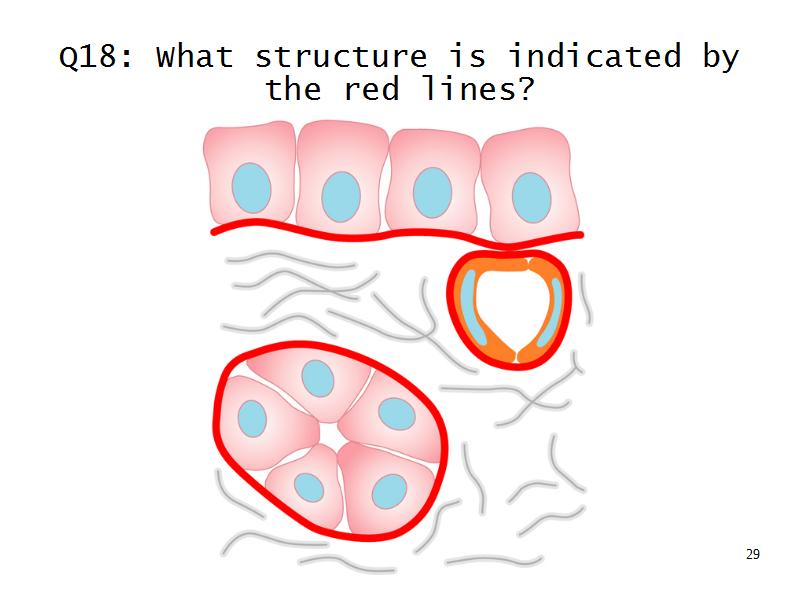

Q13: Name 1 epithelium for each.

- Kidney =

- Liver =

Q13: Name 1 epithelium for each.

- Kidney = cuboidal, squamous

- Liver = squamous, cuboidal